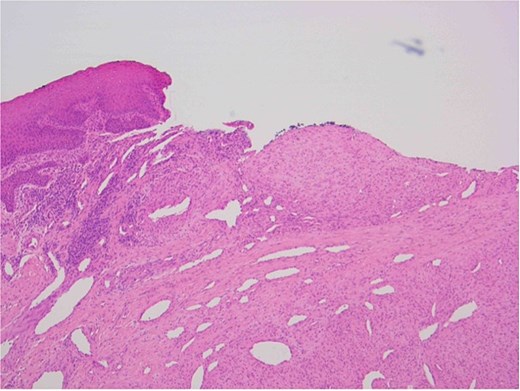

The patient underwent a biopsy of the lesion. Histopathological analysis revealed spindle cell proliferation arranged in a fascicular growth pattern, dilated hemangiopericytoma-like vessels, and a central myeloid nodule. Immunohistochemical staining was positive for smooth muscle actin (SMA), with no evidence of cellular atypia (Figs 5–7).

Oral squamous mucosa with underlying bland spindle cell proliferation showing fascicular growth and dilated haemangiopericytoma-like vessels and a myoid nodule centrally.